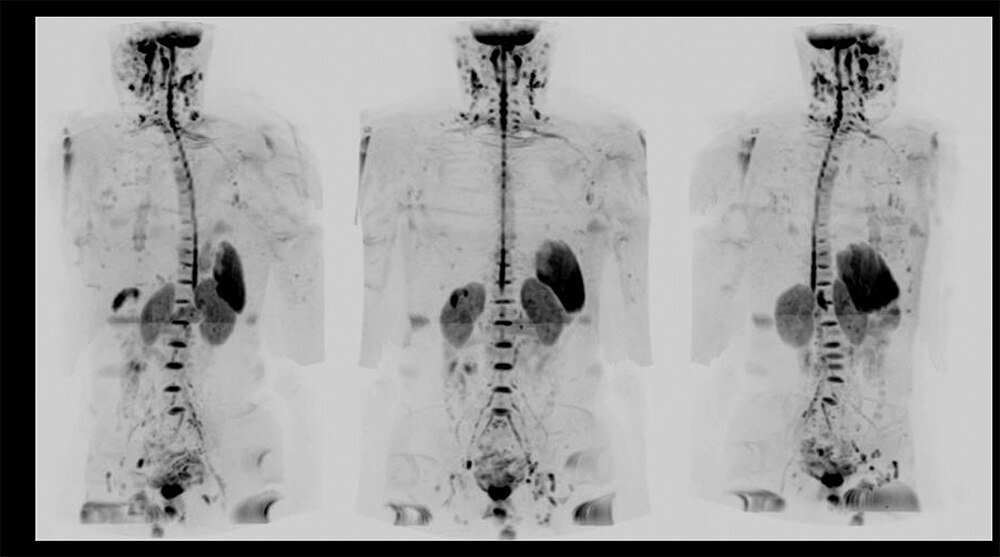

Case1 泌尿器科:前立腺癌の骨転移検索目的

70代、男性。PSA著明高値(6000ng/mL)の前立腺癌で転移検索目的にてWBDWIを施行した。WBDWIで上腕骨、肋骨、横突起、骨盤内リンパ節転移が認められる(図10)。この症例はPSAが著明高値であったため、CTを撮影せずにWBDWIを撮像することで迅速な治療方針決定に貢献することができた。依頼医からもWBDWIは骨の情報だけでなく、リンパ節や臓器の情報も得ることができるので非常に有用であると評価が得られた。

図10 前立腺癌の骨転移検索目的